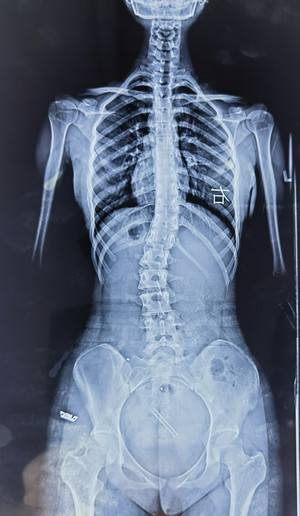

脊柱侧弯拍X片

脊柱侧弯

拍X片

我的孩子可能脊柱侧弯了,想拍一个 “ 站立式全脊柱正侧位X片 ” 。

您也可以给医生看上图,问下医生能不能拍这样的X片(并不是所有医院都有能力拍这样的X片)。